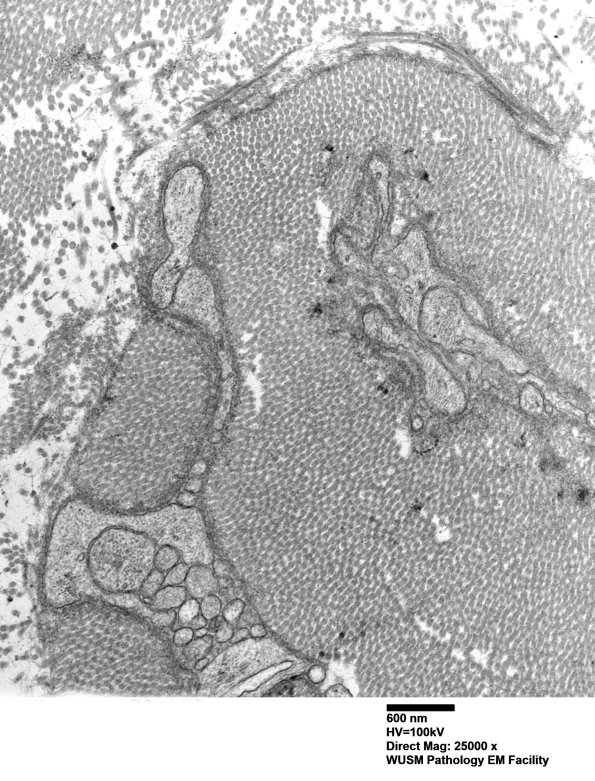

Washington University Experience | PERIPHERAL NEUROPATHY | 4 AXONAL DEGENERATION | 3 Electron Microscopy | 7A6B Chronic Degeneration (Case 33) Sural_055 - Copy

In this collection of processes and collagen it appears most processes are Schwannian in origin. (electron micrographs)